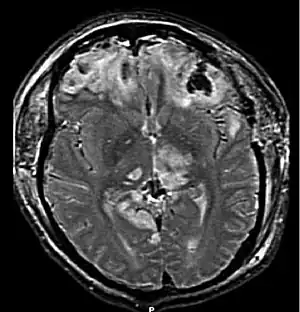

| MRI showing injury due to brain herniation | |

Brain herniation is a potentially deadly side effect of very high pressure within the skull that occurs when a part of the brain is squeezed across structures within the skull. The brain can shift across such structures as the falx cerebri, the tentorium cerebelli, and even through the foramen magnum (the hole in the base of the skull through which the spinal cord connects with the brain). Herniation can be caused by a number of factors that cause a mass effect and increase intracranial pressure (ICP): these include traumatic brain injury, intracranial hemorrhage, or brain tumor.[1]

Treatment involves removal of the etiologic mass and decompressive craniectomy. Brain herniation can cause severe disability or death. In fact, when herniation is visible on a CT scan, the prognosis for a meaningful recovery of neurological function is poor.[2] The patient may become paralyzed on the same side as the lesion causing the pressure, or damage to parts of the brain caused by herniation may cause paralysis on the side opposite the lesion.[11] Damage to the midbrain, which contains the reticular activating network which regulates consciousness, will result in coma.[11] Damage to the cardio-respiratory centers in the medulla oblongata will cause respiratory arrest and (secondarily) cardiac arrest.[11] Investigation is underway regarding the use of neuroprotective agents during the prolonged post-traumatic period of brain hypersensitivity associated with the syndrome.[17]